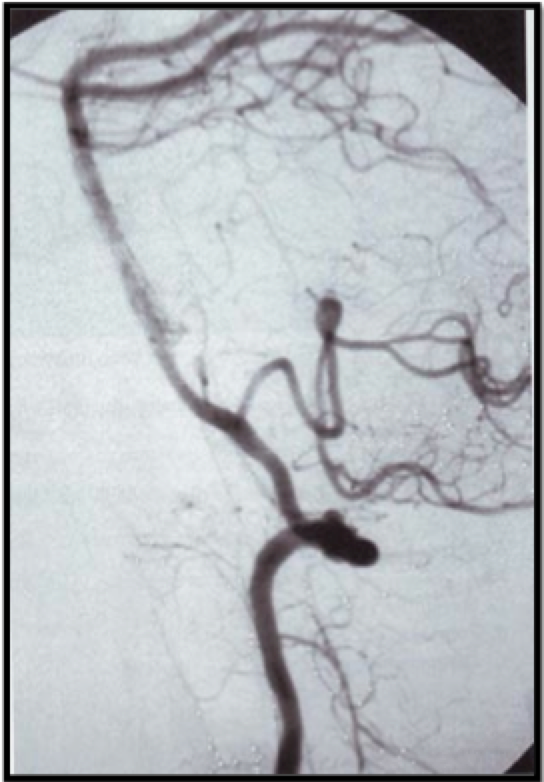

Apa yang tampak pada angiogram lateral di bawah ini ?

A. Arteri intersegmental proatlantal

B. Aneurism

C. Malformasi kavernus

D. Arteri hipoglosal persisten

E. Fistula arterial-Venus dural

B